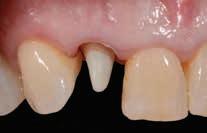

management of vital and non-vital discolored tooth preparation stump shades: A clinical case series

Two clinical case reports are presented showing different treatment approaches to differing clinical scenarios of partial coverage veneer and full coverage crown restorations, respectively.

Case: A 43-year-old Caucasian male patient presented with a history of trauma to his maxillary central incisor teeth, which had discolored over time. His chief complaint was not only the discoloration of the central incisor teeth but also the shape, form, and facial contour that had been attempted with composite resin restorations. (A) After crown removal of #7, the metal post was covered with a white composite resin core material; (B) A gold post foundation restoration was used on tooth #10; (B) Stump shade photographs were taken after tooth preparation; (C) The intaglio surface of the crown restorations with the white opaque liner added short of the cervical margin; and (D) Extraoral smile view of the patient demonstrating esthetic integration of the crown restorations.

Feldspathic ceramics should be considered when customization of stump shade correction and equalization is required with minimum facial reduction with veneer restorations. Translucent zirconia (5 mol% Y2O3) can be used to mask metal posts and core restorations on non-vital teeth using an opaquer material that is infused into the intaglio surface in the green state.